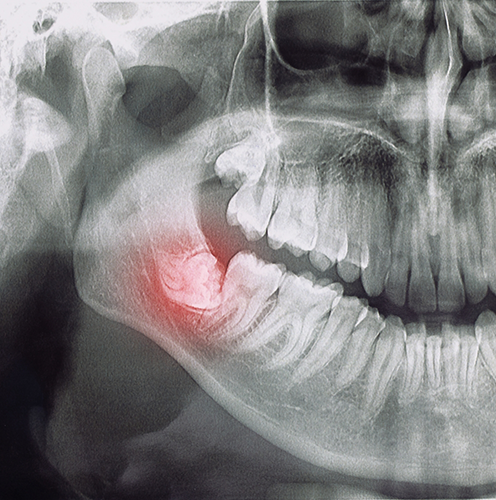

Impacted Supernumerary Teeth Extractions

Most people develop a total of 32 permanent teeth, including wisdom teeth. But did you know that some patients end up growing additional teeth beyond that? These are called supernumerary teeth, and when they become impacted below the gumline, they often require surgical removal—otherwise, they can interfere with the other teeth and lead to other oral health issues. At our Danville office, Dr. Sarcos leverages her advanced surgical training to evaluate and remove these unnecessary teeth safely and effectively.